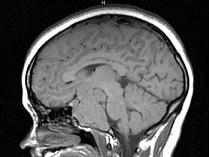

问题 女,26岁,垂体腺瘤切除术后,左眼视物模糊,请根据所提供图像,选择最可能的诊断()

选项 A.鞍区脑膜瘤 B.(垂体)复发性嫌色细胞腺瘤 C.脊索瘤 D.神经纤维瘤 E.颅咽管瘤

答案 B